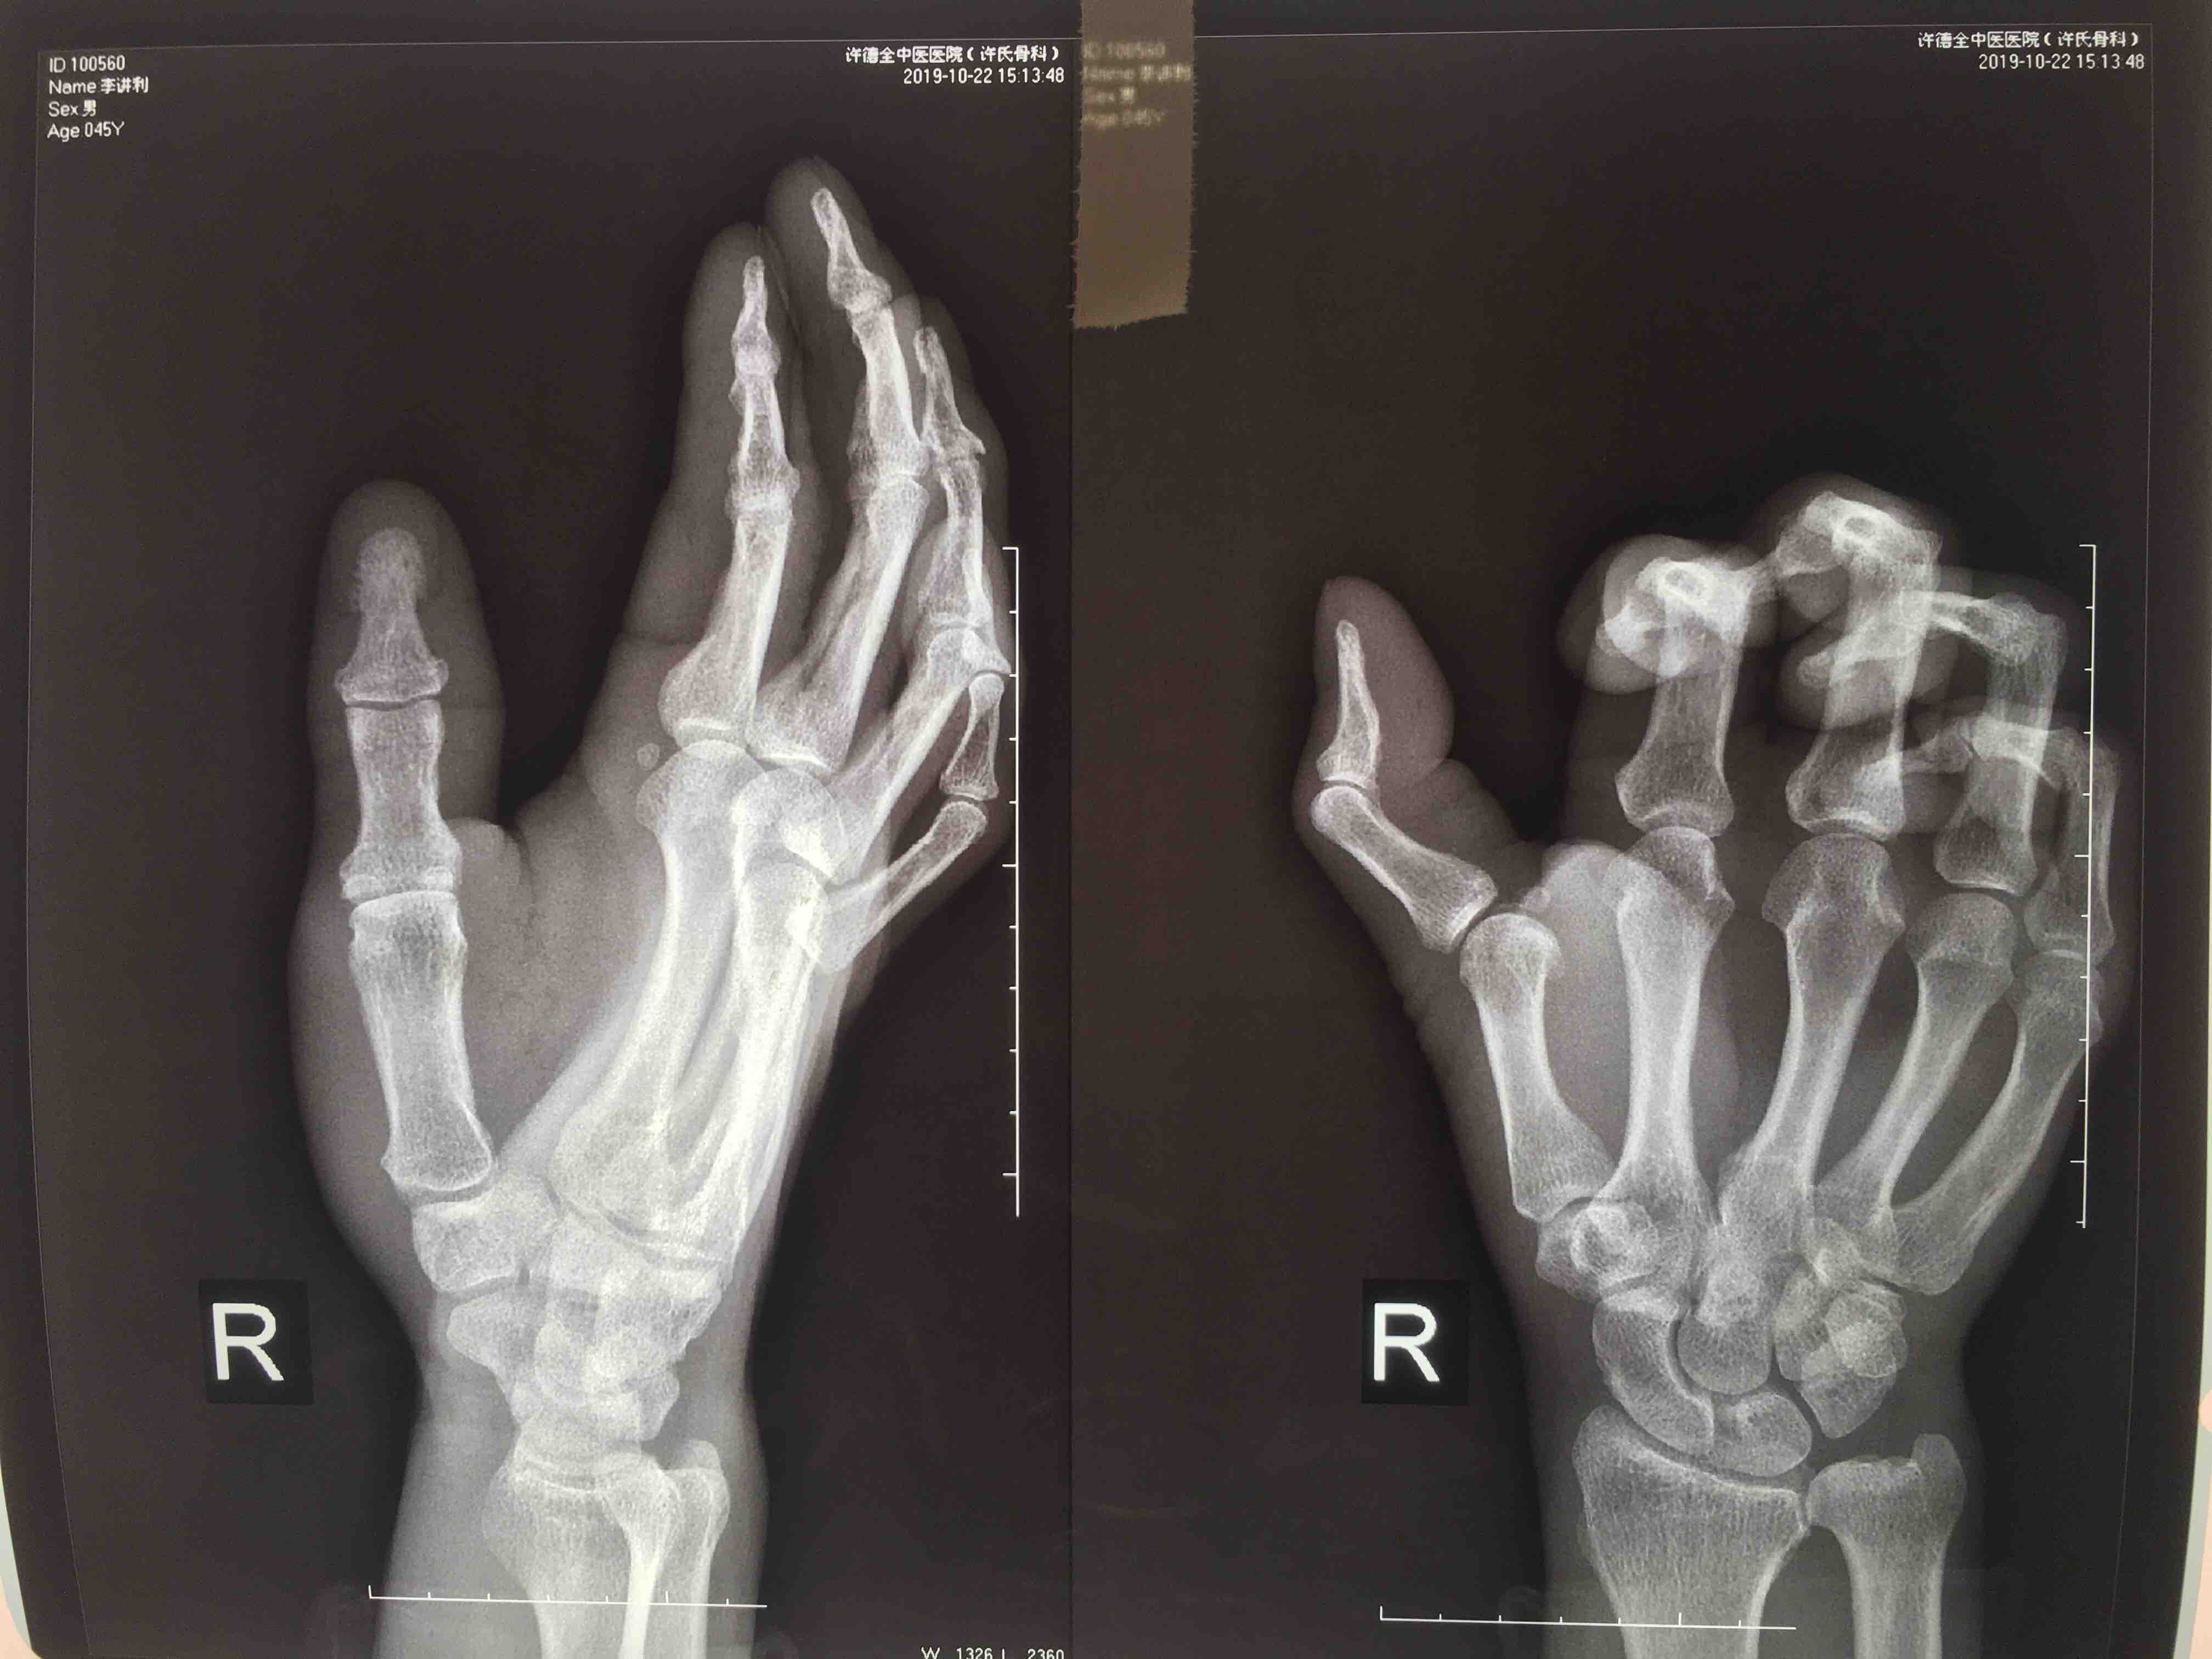

摔伤后右手拇指肿痛,畸形,活动受限4天。既往身体健康,无特殊不良嗜好。

生命体征平稳,心肺复未见异常。右拇指锤状畸形,局部皮色皮温正常,压痛,伸指功能受限,末梢血运感觉正常。

诊断右拇指锤状指在神经阻滞麻醉下切复重建伸指功能,术后抗炎,消肿等处理。